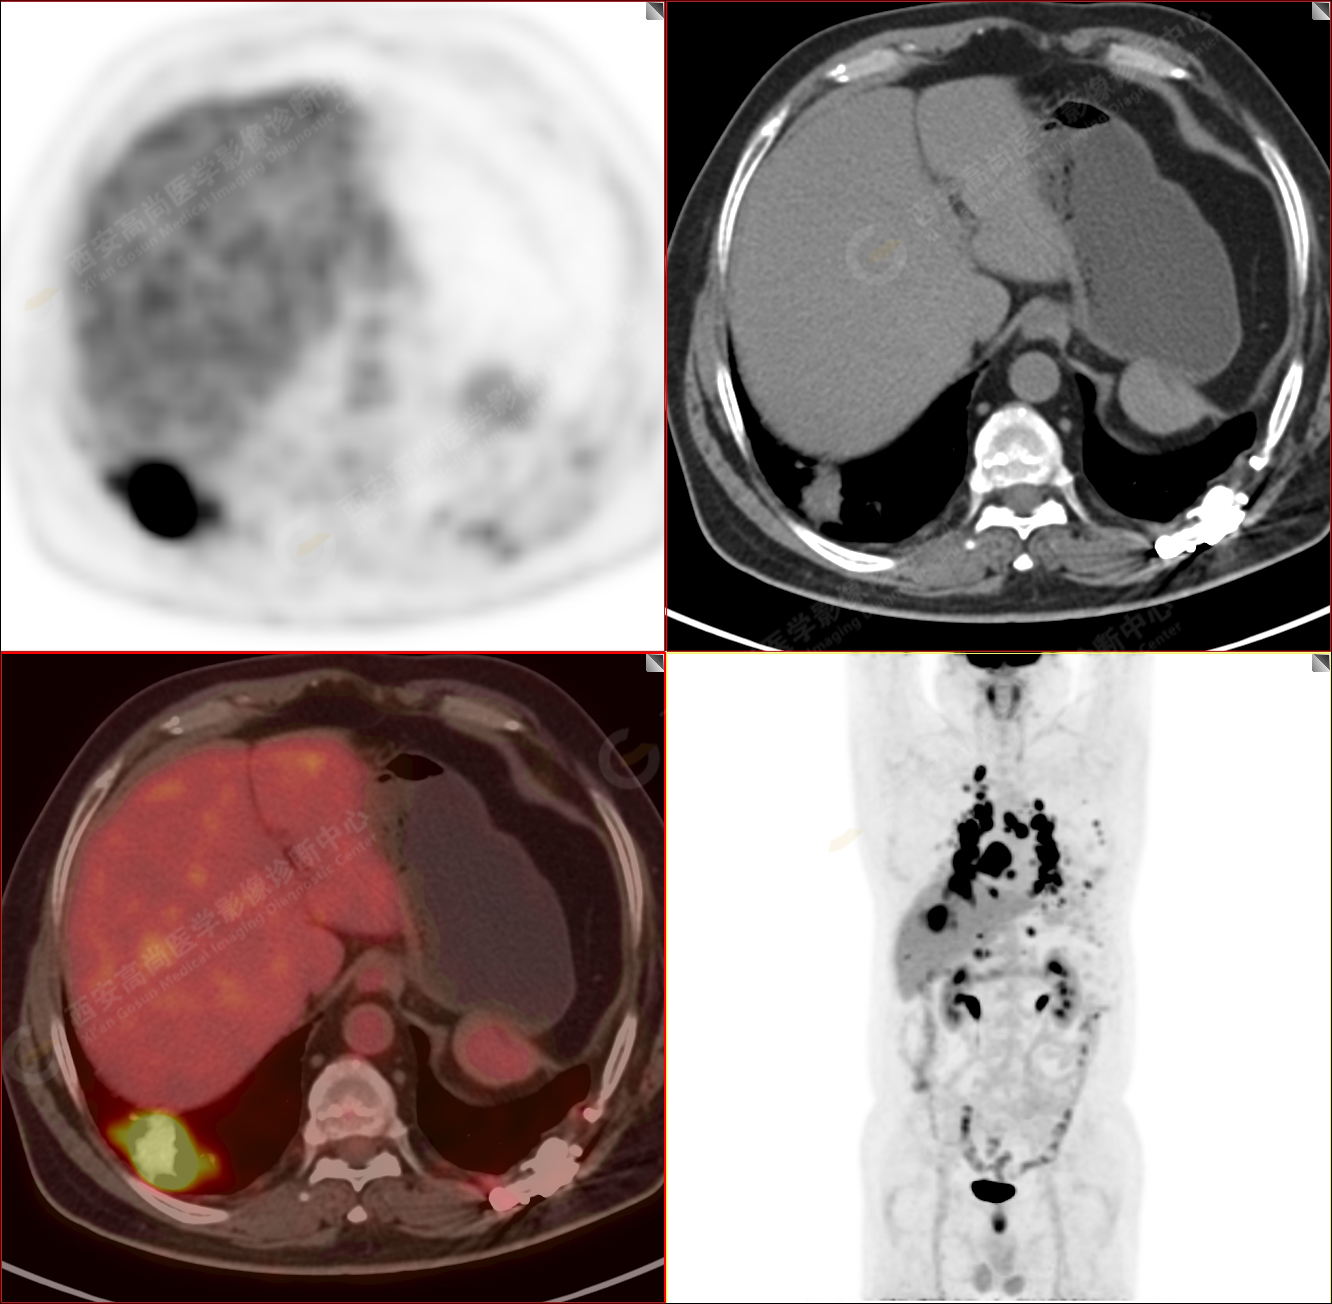

PET/CT-MR診斷結(jié)節(jié)病雙肺及全身多發(fā)淋巴結(jié)廣泛累及1例【西安高尚病例】

男性,53歲,頭暈半月入院,CT發(fā)現(xiàn)肺內(nèi)腫塊,雙肺多發(fā)大小不等實(shí)性及粟粒樣結(jié)節(jié),雙肺門(mén)及縱隔多發(fā)腫大淋巴結(jié)。病程中無(wú)發(fā)熱、胸悶氣及胸部不適。既往:左側(cè)肋骨外傷史。

PET/CT圖像